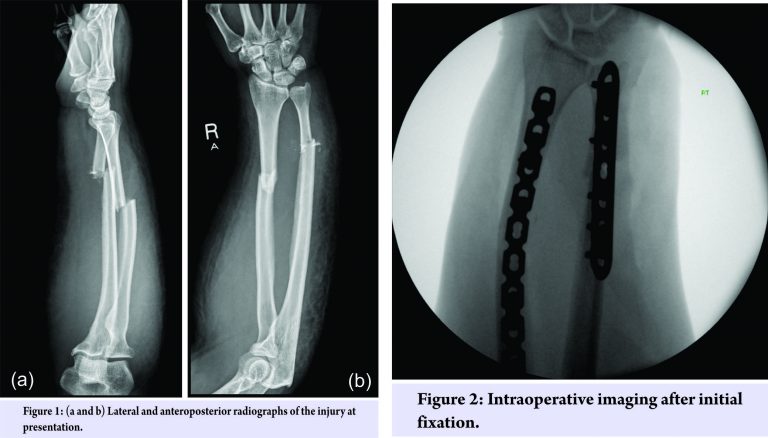

A 40-year-old White British female who mobilized in a wheelchair due to NMO presented to the emergency department in our center with a swollen, hot, painless right forearm. This patient had no current evidence of optic neuritis. She was treated with rituximab, a monoclonal antibody directed against the CD20 antigen. The arm had been in this condition for 8 days, and the patient had taken antibiotics for what was presumed to be an infection. However, the forearm gradually worsened, leading to deformity and instability. After clinical evaluation, the forearm was placed in a cast, and a plain radiograph X-ray was taken to investigate bone fracture (Fig. 1). Comminuted fractures through the mid-radius and ulna were confirmed, and a significant soft-tissue swelling was also noted. Diagnoses considered for her symptoms were cellulitis, stress fractures of the radius and ulna, and pathological fractures of the radius and ulna due to malignancy or osteoporosis. Once instability was clinically evident, the presence of a fracture became obvious. Although this did not exclude the possibility of infection, the C reactive protein and white blood cell count were not suggestive of this differential. It was only after samples of bone were examined histologically that the presence of a malignancy was excluded. The presence of osteoporosis could not be completely excluded without a dual-energy X-ray absorptiometry bone density scan. However, since this patient was not on steroidal therapy for NMO but rather a biologic drug and given her young age, osteoporosis was deemed unlikely. This patient was pre-menopausal with a regular cycle and had no gynecological history of note. Stress fractures of the radius and ulna were the diagnosis most consistent with her symptoms, imaging, and histology.

Since the patient was dependent on her upper limb to mobilize and transfer weight, we felt that it was important to stabilize the forearm contrary to usual practice. Therefore, the patient was listed for an open reduction and fixation of both the radius and ulna. Intraoperatively, the radial fracture was found to be simple with little comminution. A ten-hole locking compression plate was selected with a reasonable working length and then contoured to respect the radial bow. The ulnar fracture was found to be comminuted with rounding of the fracture ends, suggesting that this had been partially fractured for some time, indicative of a fatigue fracture. Fixed-angle (locking) plates on both radius and ulna were used to minimize the risk of construct failure through implant cut-out, about which the patient would be unaware owing to her lack of sensibility in the arm.Bone samples from the fracture site were sent for histology to exclude malignancy, although this seemed unlikely from the macroscopic appearance of the fracture site. Further, the distal radioulnar joint was found to be stable, and the radiographs (Fig. 2) were satisfactory.